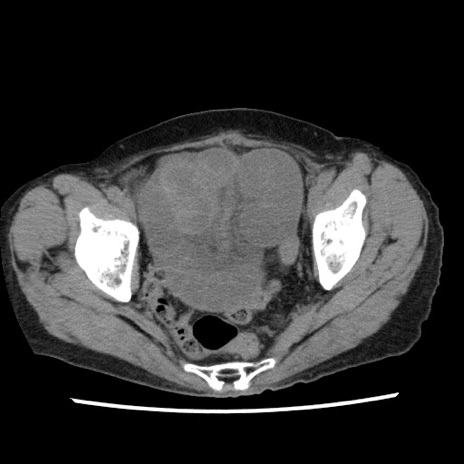

症例1(横断像)

【症例】80歳代女性

【主訴】腹痛

【現病歴】8時間前から腹痛あり来院。

【既往歴】糖尿病、脂質異常症、子宮体癌にて子宮全摘術

【身体所見】意識清明・会話良好だが腹痛で苦悶様、全腹部にわたって反跳痛と圧痛あり

【データ】WBC 13600、CRP 0.14、LDH 224、CK 90